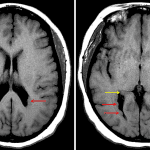

CT

- Nodularity along the ependymal surface of both lateral ventricles, which is similar in attenuation to gray matter

MRI

- Nodularity along the ependymal surface of both lateral ventricles, which follows gray matter signal on all sequences

- No corresponding enhancement or susceptibility artifact

- No substantial intracranial mass effect or evidence of hydrocephalus

Gray matter heterotopia